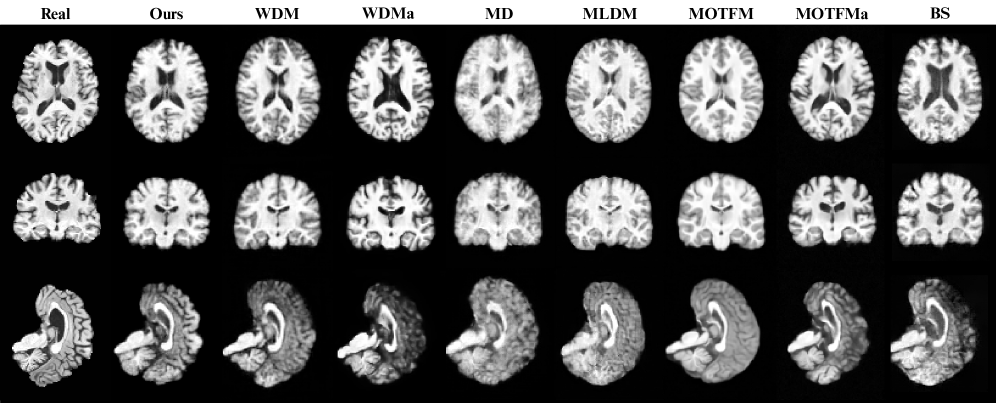

Figure 3: Visual assessment of image fidelity and realism for different 3D brain MRI synthesis models. Each column displays standard Axial, Coronal, and Sagittal views for the real reference scan (Subject of 72 years old) and specified generative method (Ours is RFM 10 steps).

Figure 3 shows representative samples generated by each model. The FlowLet-generated volume exhibits anatomically coherent structures with well-preserved cortical folding, clearly segmented cerebellum, and identifiable subcortical regions such as the hippocampus and basal ganglia. In contrast, baselines display varying degrees of anatomical degradation, including blurring, over-smoothing in cortical areas or loss of details in posterior fossa structures. These observations suggest that FlowLet better preserves complex anatomical features while minimizing common generative artifacts.